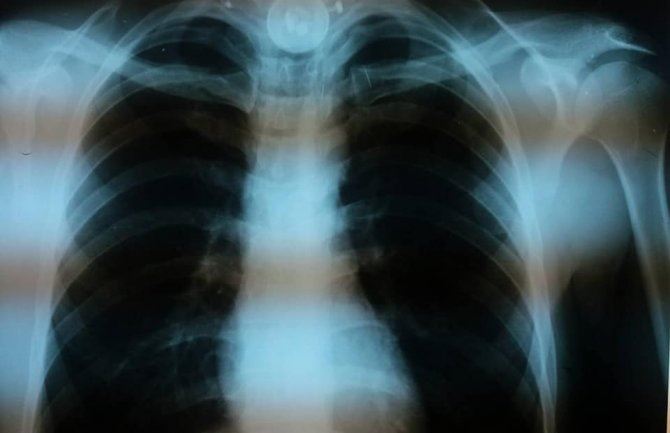

Naime, u dramatičnoj situaciji su izvadili zadesno progutano strano tijelo iz jednjaka pacijenta, objavljeno je na Facebooku.